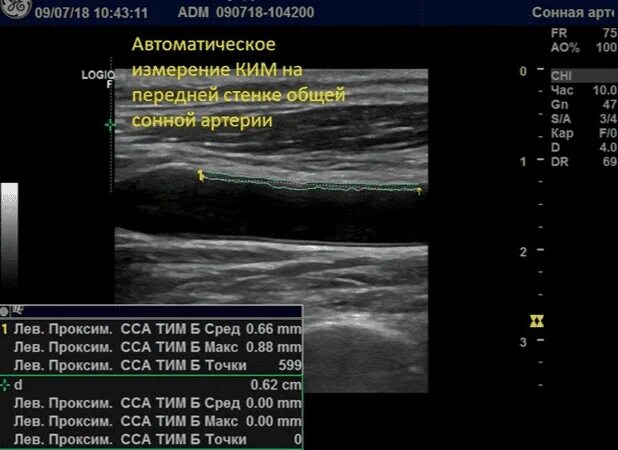

Сделать узи сонной артерии